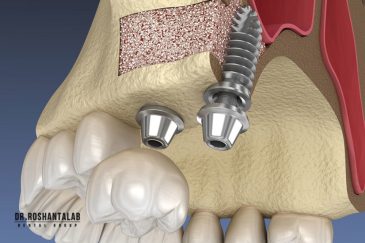

🔸جراحی پیشرفته نظیر سینوس لیفت